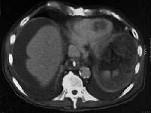

问题 87岁的甲状腺癌转移患者,傍晚行CT检查后死亡。CT图像如图所示,请选择正确的描述和结论 ( )

选项 A、考虑为右心室血栓 B、黏液瘤 C、该充盈缺损累及右心室流出道 D、未见异常发现 E、右心室见一不规则低密度充盈缺损

答案 ACE